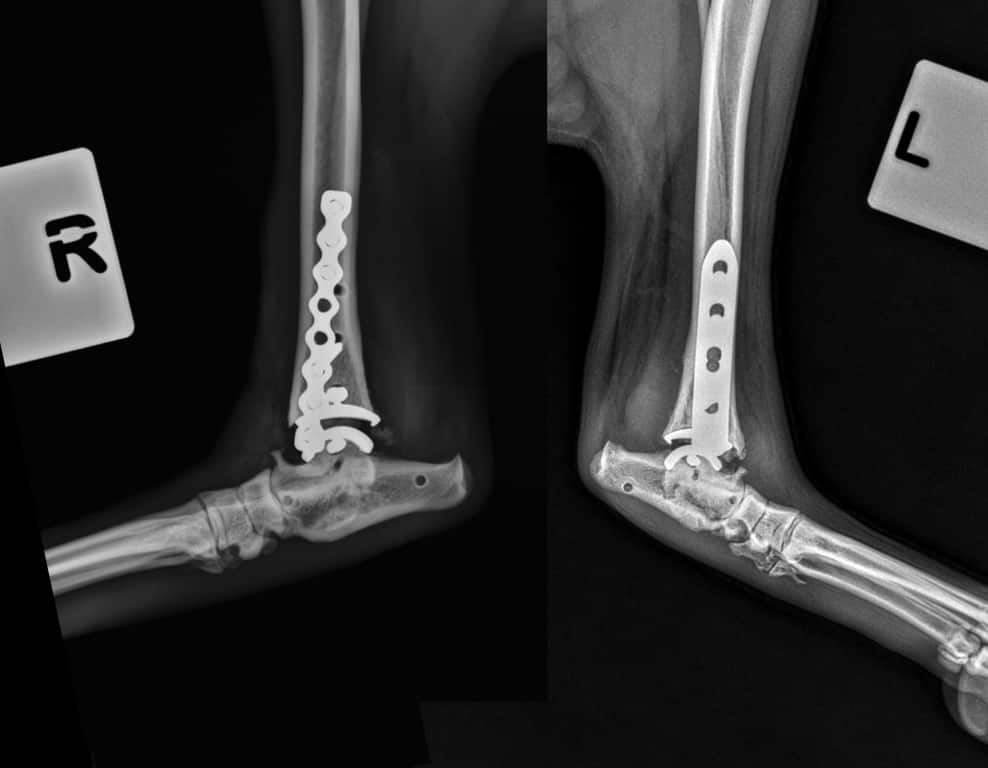

One of the UK’s top animal hospitals has carried out a world-first double ankle replacement on a dog.